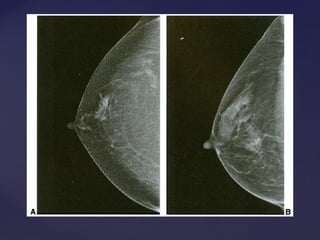

Padrão mamográficoPadrão mamográfico

Descrição Acurácia Diagnóstica

Lipossubstituídas (até 25% de tecido

glandular)

Muito alta

Parcialmente lipossubstituídas (26 a 50% de

tecido glandular)

Alta

Densas e heterogêneas

(51 a 75% de tecido glandular)

Limitada

Muito densas (>75% de tecido glandular) Limitada